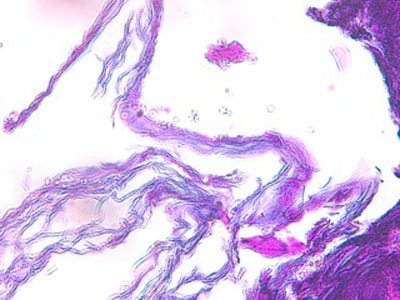

Histologie : L ‘épiderme et les infundibula folliculaires sont hyperplasiques, sièges d’une acanthose régulière d’intensité modérée, associée à une hyperpigmentation et à une hyperkératose tantôt orthokératosique, tantôt focalement parakératosique d’intensité modérée. La couche cornée est ainsi épaissie, croûteuse, stratifiée. L’épiderme et les structures infundibulaires, sont le siège d’une régulière exocytose de petits lymphocytes et plus rarement de neutrophiles. Dans le derme, les sacs folliculaires sont rarement rompus et les glandes sudorales font l’objet de remaniements inflammatoires chroniques, plasmocytaires. Au sein de la kératine libre péri-pilaire et au sein de la couche cornée de l’épiderme, on observe de rares hyphes mycéliennes PAS positives.

dermatophytose-atypiqueh2-jpegEFH2